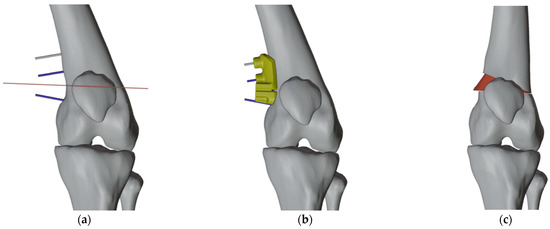

2.4.2. PSI Design for the Left Femur